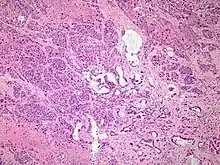

Micrograph of pancreatic ductal adenocarcinoma (the most common type of pancreatic cancer), H&E stain

The most common form of pancreatic cancer (adenocarcinoma) is typically characterized by moderately to poorly differentiated glandular structures on microscopic examination. There is typically considerable desmoplasia or formation of a dense fibrous stroma or structural tissue consisting of a range of cell types (including myofibroblasts, macrophages, lymphocytes and mast cells) and deposited material (such as type I collagen and hyaluronic acid). This creates a tumor microenvironment that is short of blood vessels (hypovascular) and so of oxygen (tumor hypoxia).[2] It is thought that this prevents many chemotherapy drugs from reaching the tumor, as one factor making the cancer especially hard to treat.[2][3]